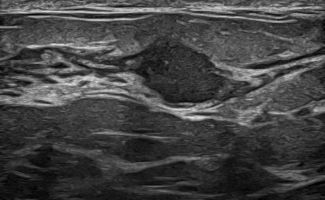

Elastography can highlight the elasticity of a lesion, indicating whether it is hard or soft. Through this technique, we can assess the nature of the lesion, providing indications of whether it is benign or malignant. Additionally, with the contribution of Color Power Doppler and B-Flow, we can monitor the vascular flow within the lesions, offering even more information about the type and nature of the abnormality.

In addition to breast examination, Breast Ultrasound also includes the examination of the axillary regions. Through this process, we detect any presence of lymph nodes, and with the help of Elastography, we can evaluate them.